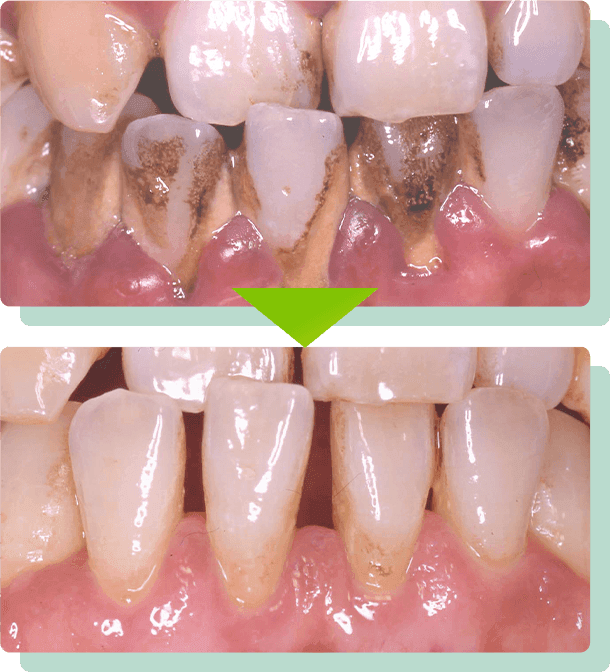

プラークや歯石の除去

日頃のブラッシングだけでばどうしても磨ききれないところがあるので、定期的なプロの歯石除去を行います。

02歯石除去

専用の器具を使って、こびり付いた歯石を取り除きます。

03歯の汚れや着色を除去

微粒子研磨ペーストを使用して、歯の表面や根元の部分を美しく磨き上げます。

このとき、歯ブラシで落とすことができないステイン(ヤニや茶渋など)や汚れの塊などをキレイに落とします。